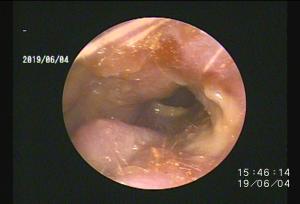

今回アップした動画は慢性外耳炎の中でも管理が困難な「耳垢腺過形成」による症例への治療動画になります

このような症例は管理が困難なため「全耳道切除」が一般的ですが、耳を摘出する手術は侵襲性が高いためなるべく避けたいところです。顔面神経麻痺などの副作用が懸念されます。

当院では内視鏡レーザー治療による緩和処置をすることで点耳薬による症状の改善を期待することができます

このような症例は案外多いため、一度精査を行い適切なケアをしてあげることがおすすめされます